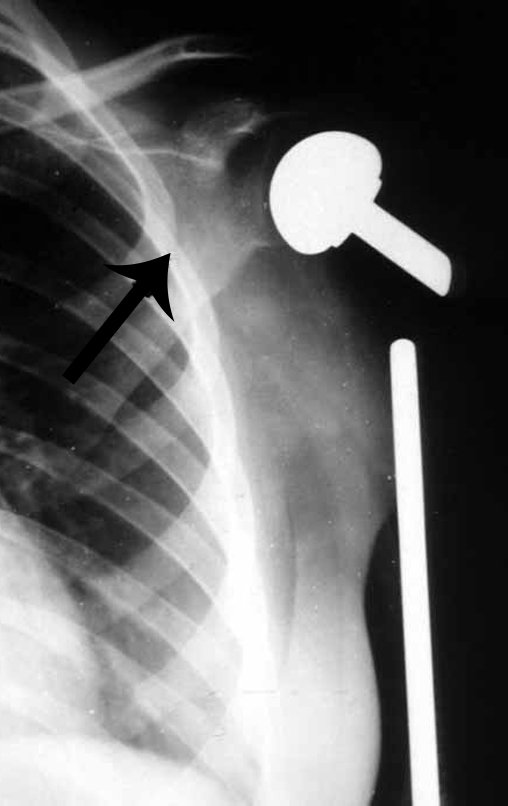

Osteossarcoma do úmero com metástase pulmonar Endoprótese de Polietileno - Metastectomia

Vídeo 2: Função em 06/08/2014, com 27 anos de acompanhamento de ressecção de osteossarcoma do úmero esquerdo e reconstrução com endoprótese não convencional de polietileno.